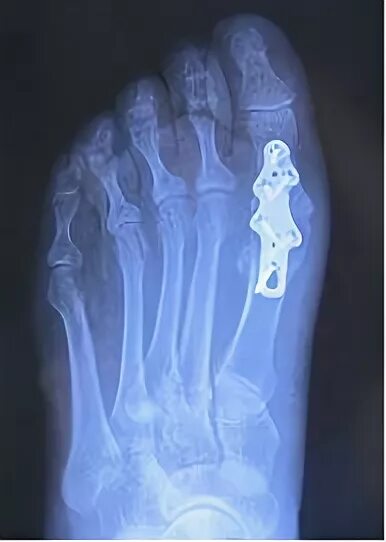

Артроз 1 степени плюснефалангового сустава стопы